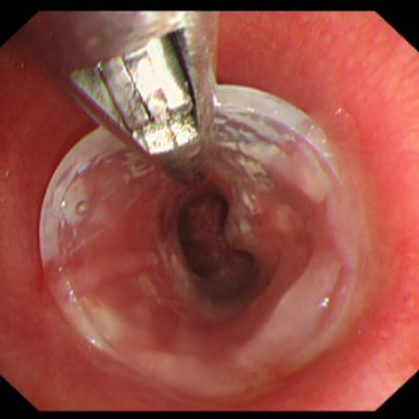

经过术前的充分准备,患者在全麻下,用可弯曲支气管镜引导插入法插入硬镜,通过高频电刀放射状切开狭窄环,再予气道球囊扩张器扩张气道置入硅酮支架,并置入喉罩复苏,最后成功为患者实施硬质支气管镜技术。术后,患者气道通畅,无呼吸困难、气促等症状出现,对比术前生活质量得到明显改善。

高频电刀切开狭窄环